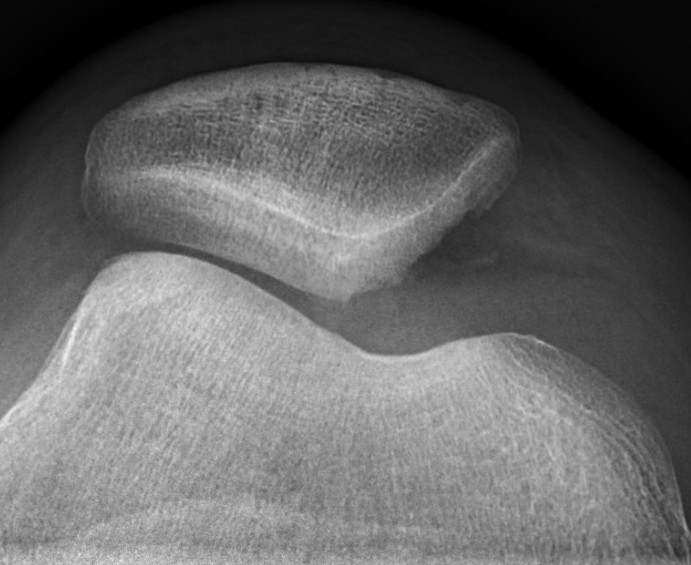

Xray

Look for osteochondral fractures

- skyline xray: suprapatella pouch

Large medial patella osteochondral fracture